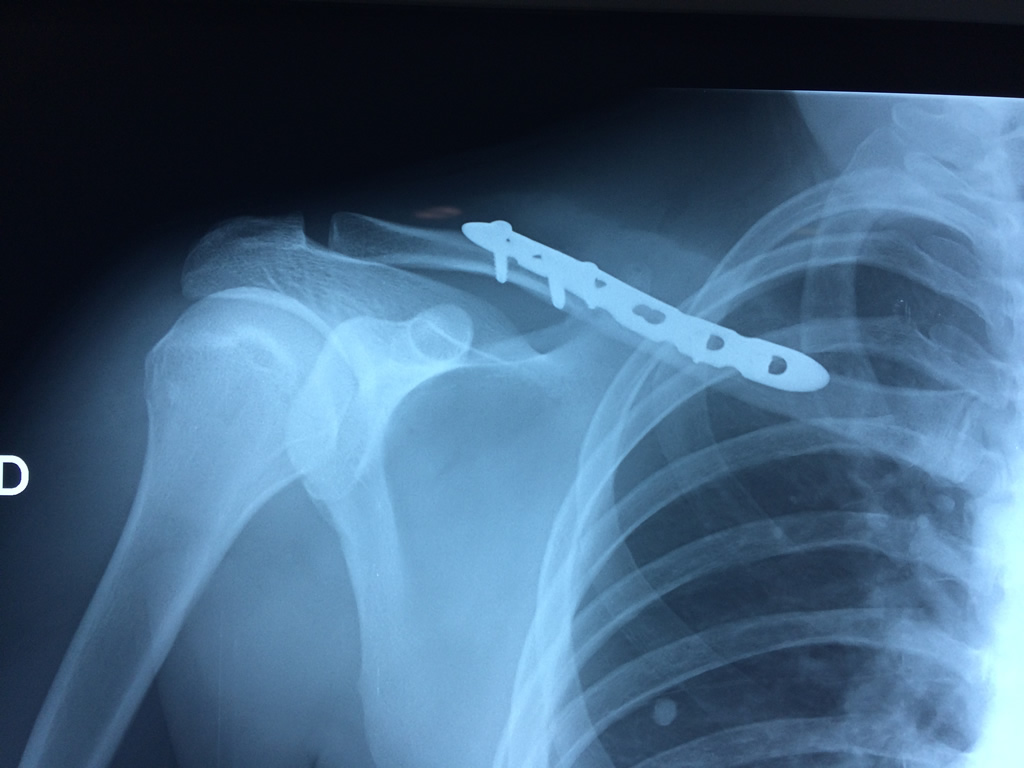

La clavícula es un hueso largo, con forma de "S" itálica, situado en la parte anterosuperior del tórax. Junto con la escápula forman la cintura escapular. Se puede palpar por toda su longitud y se extiende del esternón al acromion de la escápula, siguiendo una dirección oblicua lateral y posterior.